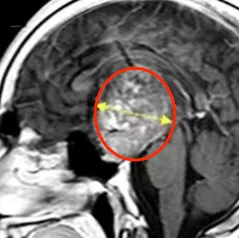

44岁女性莱娜,长期反复的癫痫发作已经让她苦不堪言,检查发现右侧脑室内见一巨大肿瘤正在扩散。 术前MRI 脑肿瘤相关性癫痫是癫痫的一个类型,通常由颅内肿瘤本身或其占位效应导致病灶...